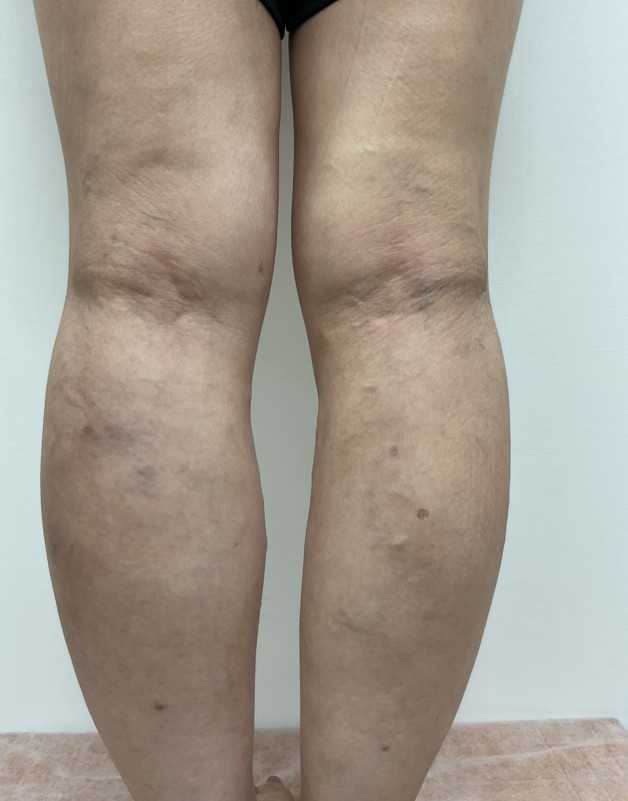

術前

術後